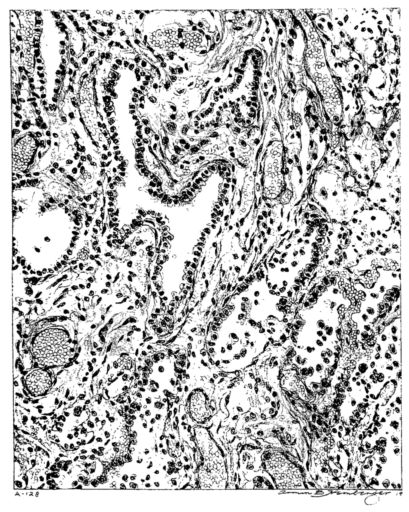

FIG. I. AUTOPSY NO. 99. ACUTE HEMORRHAGIC AND ULCERATIVE LARYNGOTRACHEITIS.

FIG. I. AUTOPSY NO. 99. ACUTE HEMORRHAGIC AND ULCERATIVE LARYNGOTRACHEITIS.

Early in the disease the congestion and the hemorrhages that have been described in the mucous membrane of the nasopharynx (14 and 94) are also conspicuous features in the lining of the trachea and bronchi (Fig. I). This membrane is swollen, turgid, red, and covered by a copious, mucous exudate which may be clear, but much more frequently is blood-stained or opaque and yellowish in color. The blood, variable in amount, may be fresh and red; and after the mucous exudate on the surface is removed, more intense red foci stand out on the congested base (47, 90, 157). Frequently, as the bronchi are approached, the red color of the mucosa becomes more intense and may have a garnet tinge. Membranes such as are encountered in the more usual necrotizing inflammatory processes, like diphtheria, have not occurred in the trachea and larger bronchi in this series (108, 128, 157).[3] The exudate peels off readily, and as indicated above, leaves a velvety red surface, 14dotted here and there with darker or more intensely red foci. Small ulcerations of the mucosa occur, but are inconspicuous (82, 156). As the finer ramifications of the bronchi are approached, the accumulation of the exudate in their lumina becomes more and more marked, and on cross section of the lung, they often stand out conspicuously on account of their increased size and projecting, seromucous, blood-stained content (101, 149, 162).